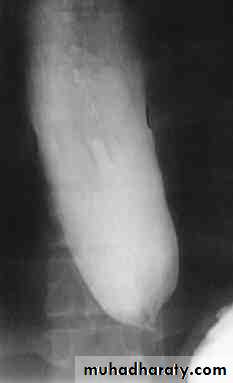

PULSION DIVERTICULUM• Due to raised intra-luminal tension

• 2- Chocking after meal .

• 3- In cervical portion at level of C5

• 4- Posteriorly (Killience dehiscent)

• 5- Lateral view show increased pre-vertebral space with air fluid level.

• 6- Confirmed by Ba. Swallow.

TRACTION DIVERTICULUM

Out pouching of lumen laterally due to fibrosis & adhesions( post-Tb.)

2-In the middle third at level of hilum

3- Up ward direction of diverticulum

4- Irregular base

On the far left a traction diverticulum (arrow) due to hilar granulomatous disease. Calcified adenopathy (asterisk). In the middle a pulsion diverticulum (arrow) due to high intra luminal pressure.On the right multiple pulsion diverticula (arrows)